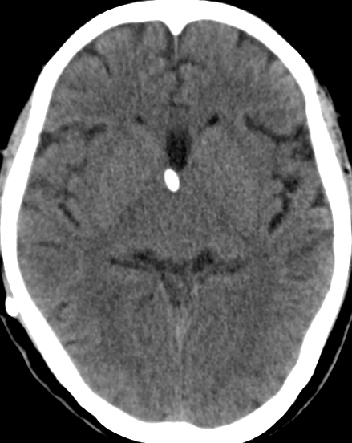

2014-10-17 CT

仍时有前额部疼痛,程度轻,调压190—200